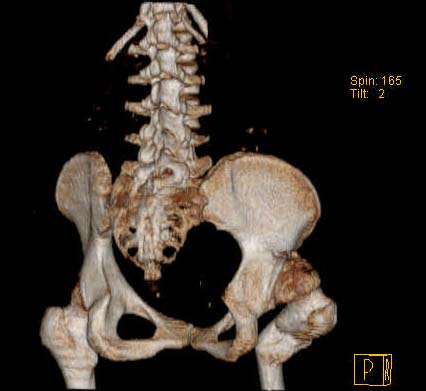

Уважаемые коллеги!Женщина, 35 летВ прошлом по поводу врожденного вывиха бедра перенесла операцию остеотомии по Шанцу

с удлинением правой ноги за счет бедра на уровне диафиза. В последнее время прогрессируют боли в правом тазобедренном суставе, порочное положение правой ноги, затруднена ходьба.Вопросы:1) Целесообразно ли эндопротезирование правого тазобедренного сустава?2) Целесообразный ли следующие действия: канал бедренной кости предполагаем вскрыть для введения ножки протеза на высоте угловой деформации, предполагаем низведение большого вертела с мышцами; протез будет подобран индивидуально, предполагается умеренная версия?В приложении рентгенограммы и трехмерная КТ.В цветном и более качественном варианте КТ размещена здесь